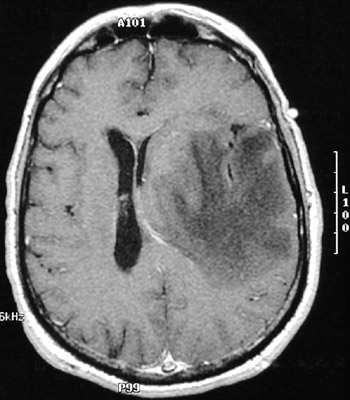

This MRI scan in axial view demonstrates cerebral edema from a nearby abscess, not seen at this level. The mass effect has resulted in a midline shift to the right and near obliteration of the left lateral ventricles.